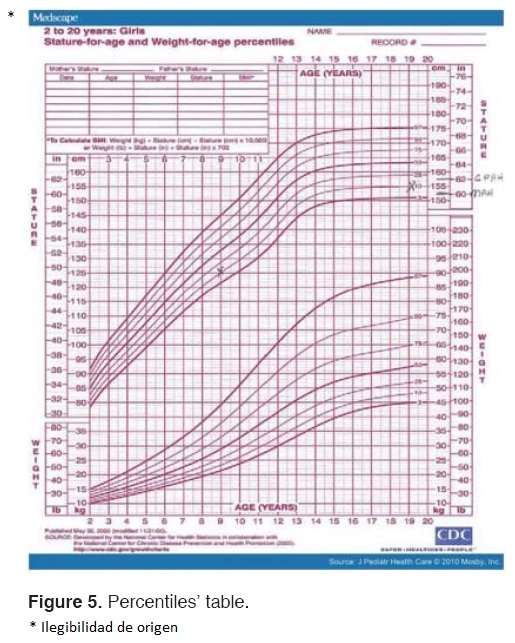

Clinical characteristics more often reported in scientific literature are retardation in physical and mental development, thickened lips and macroglossia.6,9,10,15-18 Lack of longitudinal growth can be observed at very early stages. Early diagnosis benefits the child's growth and mental capacity.19 With respect to physical development, it can be noted that patient 1 exhibited lower size and weight than recommended percentiles by institutions such as WHO (World Health Organization) and CDC (Center for Disease Control and Prevention)21,22 (Figure 5). In both cases, an enlarged tongue was found when compared to other pediatric patients. Table II describes clinical characteristic and oral manifestations of this condition.